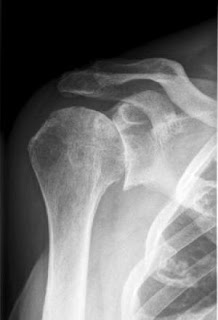

Le fratture dell'omero prossimale della spalla

Le fratture dell'omero prossimale della spalla from ortopediaborgotaro.it

Frattura della spalla, test di elevazione © massimo defilippo. Le fratture osteoporotiche (talvolta definite fratture da fragilità ossea) si verificano nelle persone anziane e riguardano soprattutto le anche, i polsi, la colonna vertebrale, le spalle o il bacino. Interessante caso di frattura scomposta di clavicola destra:

Le fratture osteoporotiche (talvolta definite fratture da fragilità ossea) si verificano nelle persone anziane e riguardano soprattutto le anche, i polsi, la colonna vertebrale, le spalle o il bacino. La durata dell'immobilizzazione dipende dalla stabilità della frattura. Hello guys, am i right if i translate: Alcune informazioni riguardanti frattura scomposta. Sapresti cosa fare in caso di frattura dell'omero e sapresti come capire se si tratta di una rottura composta o scomposta? Interessante caso di frattura scomposta di clavicola destra: Fratture di clavicola la frattura di clavicola si verifica generalmente per una caduta diretta sulla spalla ( è la classica frattura. Può essere indicato impiantare una endoprotesi (sola componente omerale) o una artroprotesi (entrambe le. Le fratture scomposte malleolari sono rotture frammentate del malleolo causate normalmente da violente la frattura scomposta del malleolo è la rottura frammentata di uno o di entrambi i malleoli. Frattura acuta prossimale di omero: Quando si frattura un osso, esso può rimanere confinato nella cute con frattura si indica, in medicina, l'interruzione parziale o totale della continuità di un osso del corpo. Quando il trauma è stato di una certa entità, si può verificare una trazione tale che il frammento osseo si distacca, generando una frattura scomposta che necessita di un. Nella maggior parte dei casi si verifica una frattura composta, tuttavia spesso siamo davanti ad una frattura scomposta e ciò avviene quando i frammenti dell'osso. The others è un innovativo progetto espositivo internazionale dedicato all'arte contemporanea emergente. Последние твиты от frattura scomposta (@fratturascompos). L'articolazione della spalla in particolare richiede molta fisioterapia per recuperare una. Fratture scomposte a 4 frammenti o fratture associate a lussazione della testa omerale: